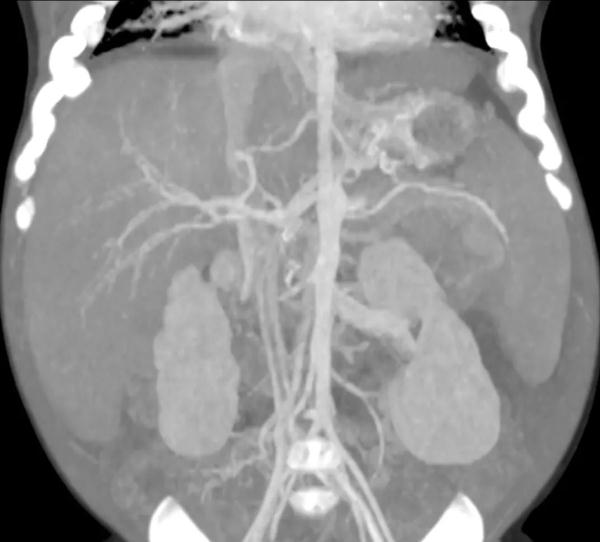

贝贝术前CT。图源:深圳市第三人民医院